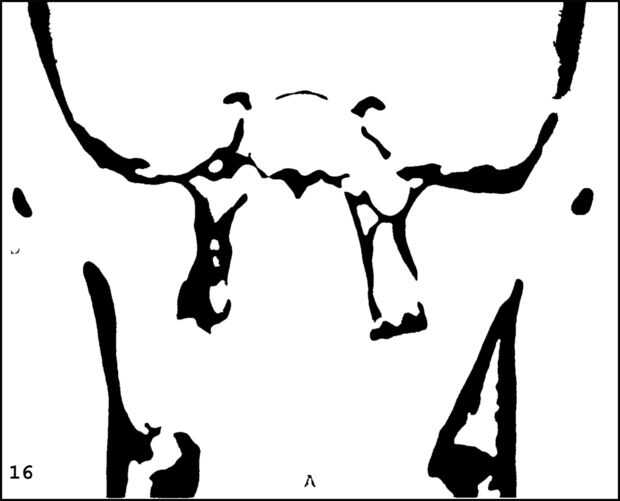

¡ Wow! Este fue por menos de 12 horas y tengo 1.000 visitas! Esto es sólo mi segundo instructable, así que estoy encantada. Decidí seguir adelante y publicar las imágenes que utiliza. Se trata de MRI de mi esposa, así que ella sólo puede tener lo mundos primer código abierto jefe. Mi lámpara utiliza solamente las primeras 16 capas, pero te di todos 34 que representa. Seguir adelante y usar estas imágenes, pero si lo haces, por favor me manden una imagen de lo que te ocurrió así que puedo hacerla sentir un poco famoso. ¡Que te diviertas!